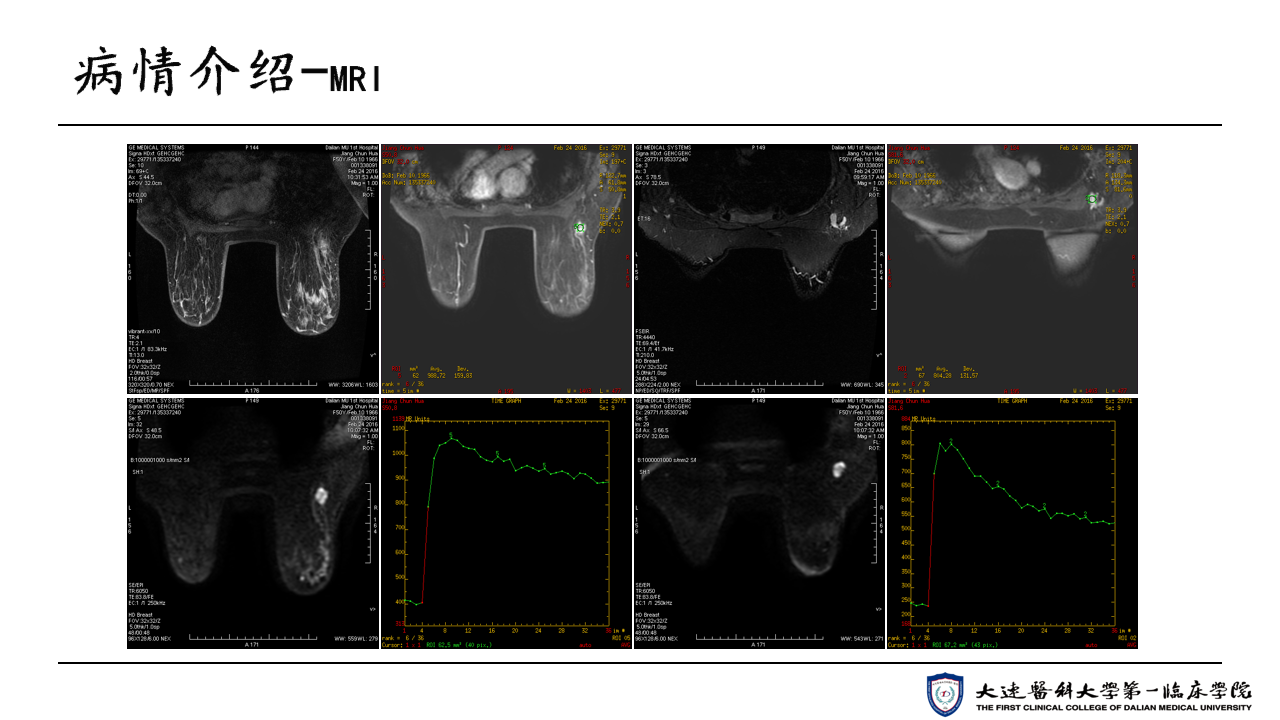

【35 under 35 ASCO放疗病例】王晓杰医生:Her-2阳性晚期乳腺癌病例

编译:王晓杰 大连医科大学附属第一医院